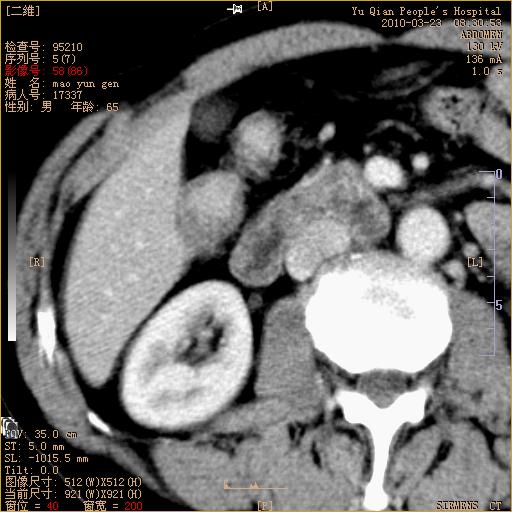

标题: CT25266:消瘦月余,前来肝部检查,请看看肠腔 [打印本页]

标题: CT25266:消瘦月余,前来肝部检查,请看看肠腔

肝区结肠占位,腺癌可考虑,建议肠镜活检。

升结肠肠壁增厚,不均强化,考虑升结肠腺癌可能性,建议肠镜检查。

1)考虑升结肠癌。2)右肾小囊肿。